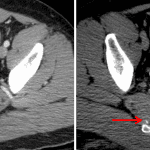

- Retained ballistic fragment in the lower left ventral abdominal wall just superficial to the rectus musculature

- Soft tissue contusion and subcutaneous gas in the right gluteal region

Likely bullet entry site in the right gluteal region with retained ballistic fragment in the lower left ventral abdominal wall just superficial to the rectus musculature.